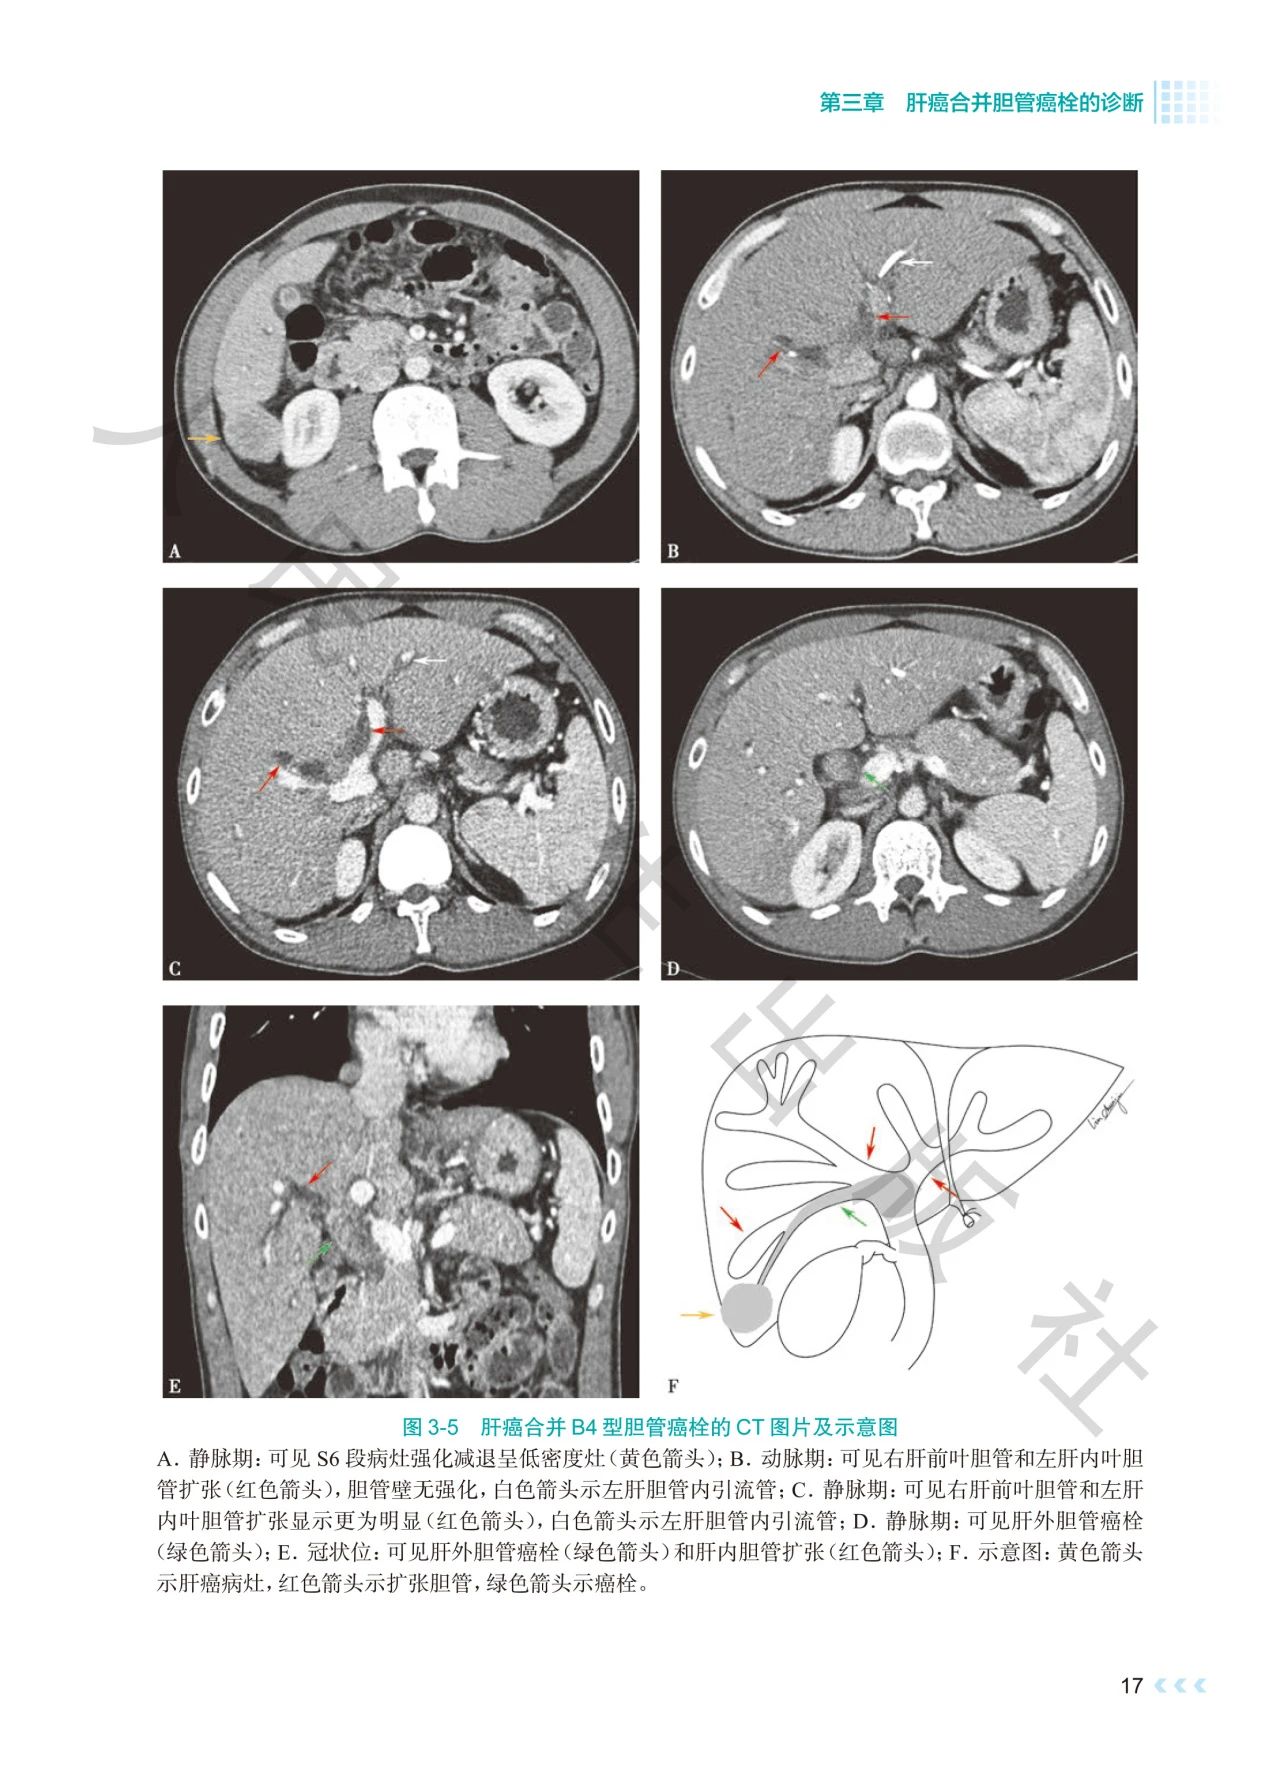

《肝癌合并胆管癌栓诊治》深入探讨了肝癌合并胆管

癌栓诊治领域的焦点问题。书中通过影像图、示意图

、手术图,详细阐述了不同分型胆管癌栓的影像学特

点及手术方式,提出q形胆总管切开取栓方法,强调解

本书通过丰富的示意图、影像图和手术图,对肝癌合

并胆管癌栓的分型、诊断策略、治疗方法等进行了深

入剖析,全面系统地总结了肝癌合并胆管癌栓领域的